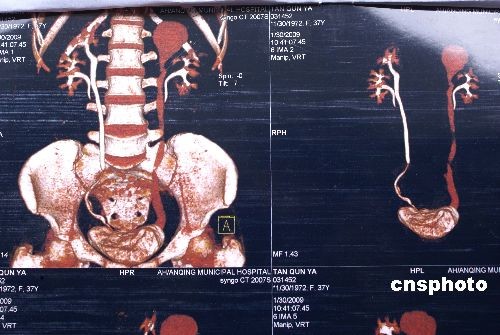

2月4日,安徽安庆市立医院,一名患肾积水女子被查出长有4个肾手术后,患者感觉良好。35岁患者檀群讶是安徽望江县龙口村人。1月30日,她左腰疼痛,到安庆市立医院泌尿外科求治,经CT检查发现,她左右两侧各长有两个肾和两个输尿管,其中左上肾出现重度积水、扩张。3日上午,医生在其后腹腔采用尿道等离子电切镜,将其异位输尿管开口上3公分蚌壳病变摘除,并在其末端输尿管重植到膀胱上。据该医院泌尿科主任朱劲松介绍,该人属先天性双肾畸形,十分罕见,大约10万人里才会遇到一个。肾主要起代谢作用,多长两个肾不会对正常生活产生影响,重植输尿管后,同样不会影响正常生活。